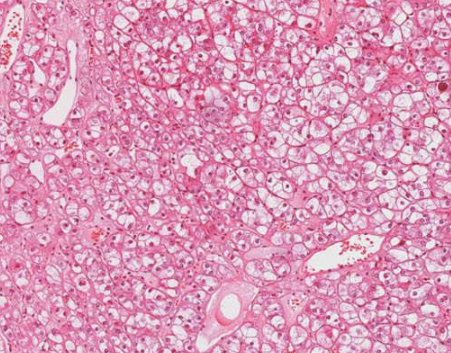

肾嫌色细胞癌是一种非常见的肾细胞恶性肿瘤,但与普通的肾细胞恶性肿瘤相比,它的恶性程度相对较低,它的形态比较特殊,恶性程度不高,根据临床医学认识,它起源于肾集合管上皮,目前在治疗此类恶性肿瘤时,大多会进行根治性切除。

全肾脏切除后往往预后效果好,与同期其他类型的恶性肿瘤相比,它的5年生存期比例相对较大。